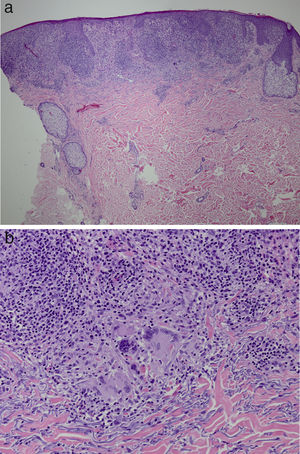

It was decided to obtain a biopsy of the lesions. Pathology study showed presence of nodular epithelioid granulomas surrounded by T lymphocytes in the dermis. In addition, areas were observed with lymphocytic epidermotropism, consistent with granulomatous dermatitis (Fig. 2a and b). Limited CD20+ B lymphocytes were detected, while CD39, CD56, CD1a, and S100 were negative. CD58 was positive for giant cells and also for some macrophages. Most of the lymphocytes of the infiltrate were marked with CD3, CD4, and CD7. The CD4:CD8 ratio was 2:1. Periodic acid-Schiff, Gomori methenamine silver, Giemsa, gram, and Fite stains were negative. Specific stains for Treponema were also negative.